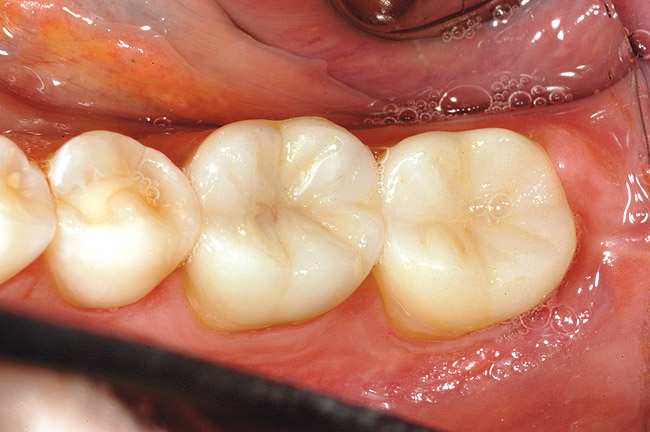

Figure 9g  The final restoration provides cuspal coverage and restores the anatomical contours of the tooth.

Figure 9g